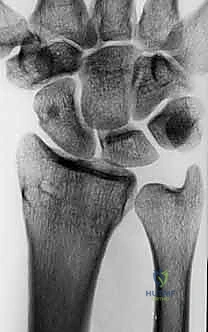

- الأشعة السينية الرقمية (X-rays): للرسغين السليم والمصاب، لمقارنة الزوايا وحساب مقدار التشوه بدقة.

- الأشعة المقطعية (CT Scan) مع إعادة البناء ثلاثي الأبعاد (3D Reconstruction): هذه الخطوة حاسمة. تتيح للدكتور هطيف رؤية العظم من جميع الزوايا، وتحديد مكان القص بدقة متناهية.